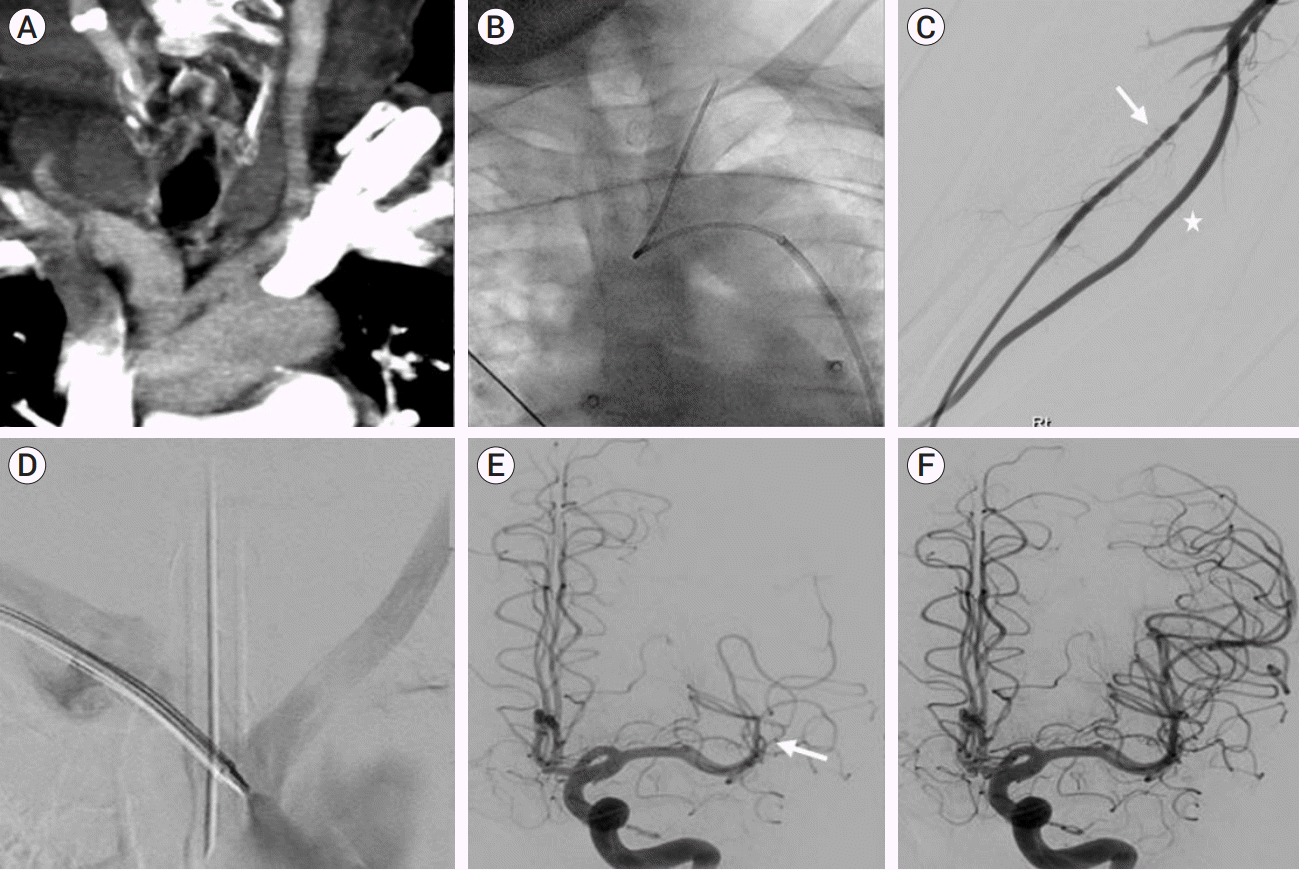

84 years old gentleman with past medical history of hypertension and diabetes, presented with acute onset of right sided weakness and global aphasia. Imaging findings were favorable for mechanical thrombectomy procedure with minimal early ischemic changes along the left insula. Review of computed tomography angiogram demonstrated occlusion of proximal M2 superior division of left middle cerebral artery with good collaterals. Assessment of aortic arch revealed a type-III combined with bovine arch variation (Fig. 1A). Initial access was obtained in the right common femoral artery using 8 French vascular sheath (Terumo, Tokyo, Japan). Considering the type-III Bovine arch, a combination of 6 French 90 cm Neuron Max guide catheter (Penumbra, Inc., Alameda, CA, USA) and 5 French 120 cm Simmons 2 Select catheter (Penumbra) was advanced over a 0.035 guidewire. Simmons 2 catheter was shaped in left subclavian artery and utilized to engage left common carotid artery (Fig. 1B). However, due to acute angulation at the origin of left internal carotid artery multiple attempts to advance guidewire were unsuccessful via this approach. Subsequently after failed femoral approach, access was secured in the right radial artery with a 6 French Slender Glidesheath (Terumo). Radial artery angiogram demonstrated small caliber radial artery with vasospasm and larger caliber ulnar artery (Fig. 1C). A combination of 6 French guide catheter along with Simmons 2 catheter was advanced into the right radial artery. However, significant resistance was encountered while advancing the guide catheter in the mid arm region due to ensuing vasospasm. Subsequently, decision was made to switch access to the ulnar artery. Initial ultrasound demonstrated right ulnar artery diameter of 3.2 mm, which was accessed under ultrasound guidance and a 6 French Glidesheath (Terumo) was placed. Subsequently the combination of Benchmark guide catheter (Penumbra) along with Simmons 2 catheter over a 0.035 guidewire was advanced through the right ulnar artery into the brachiocephalic trunk. Angiogram demonstrated bovine arch with common origin of the brachiocephalic trunk and left common carotid artery (Fig. 1D). Left internal carotid artery was easily engaged via this approach using a combination of guidewire and catheter. Initial angiogram of the left internal carotid artery demonstrated occlusion of the proximal superior M2 segment of left middle cerebral artery (Fig. 1E). Subsequently, mechanical thrombectomy was performed using SOLUMBRA technique with a combination of 4 mm×20 mm stent retriever (Solitaire revascularization device, Medtronic Neurovascular, Irvine, CA, USA) and 5 French SOFIA aspiration catheter (Microvention, Aliso Viejo, CA, USA). Thrombolysis in cerebral infarction (TICI) III reperfusion was achieved with a single pass with no evidence of distal emboli (Fig. 1F). The guide catheter and sheath were removed from the ulnar artery and non-occlusive hemostasis was secured using pneumatic wrist band. No evidence of hand ischemia was noted during or immediately after the procedure. 24 hours post procedure computed tomography demonstrated no evidence of intracranial hemorrhage and no extension of ischemic infarct. Neurological exam showed significant clinical recovery with National Institute of Health Stroke Scale (NIHSS) drop from 17 to 3. Patient was transferred to acute rehabilitation unit after 3 days. Doppler ultrasound of the distal forearm before discharge demonstrated patent flow in radial as well as ulnar artery with no evidence of dissection.

Fig. 1.

(A) Coronal computed tomography angiogram at aortic arch level, demonstrating a bovine arch. (B) Simmons II catheter is advanced in the left common carotid artery. (C) Radial artery angiogram demonstrates vasospasm along radial artery (white arrow) and larger caliber ulnar artery (white asterisk). (D) Angiogram through the Simmons II catheter placed via right ulnar artery approach, demonstrating bovine arch. (E) Left internal carotid artery angiogram demonstrating proximal M2 superior division occlusion (white arrow). (F) Post mechanical thrombectomy angiogram shows complete reperfusion of the left middle cerebral artery (MCA) territory.